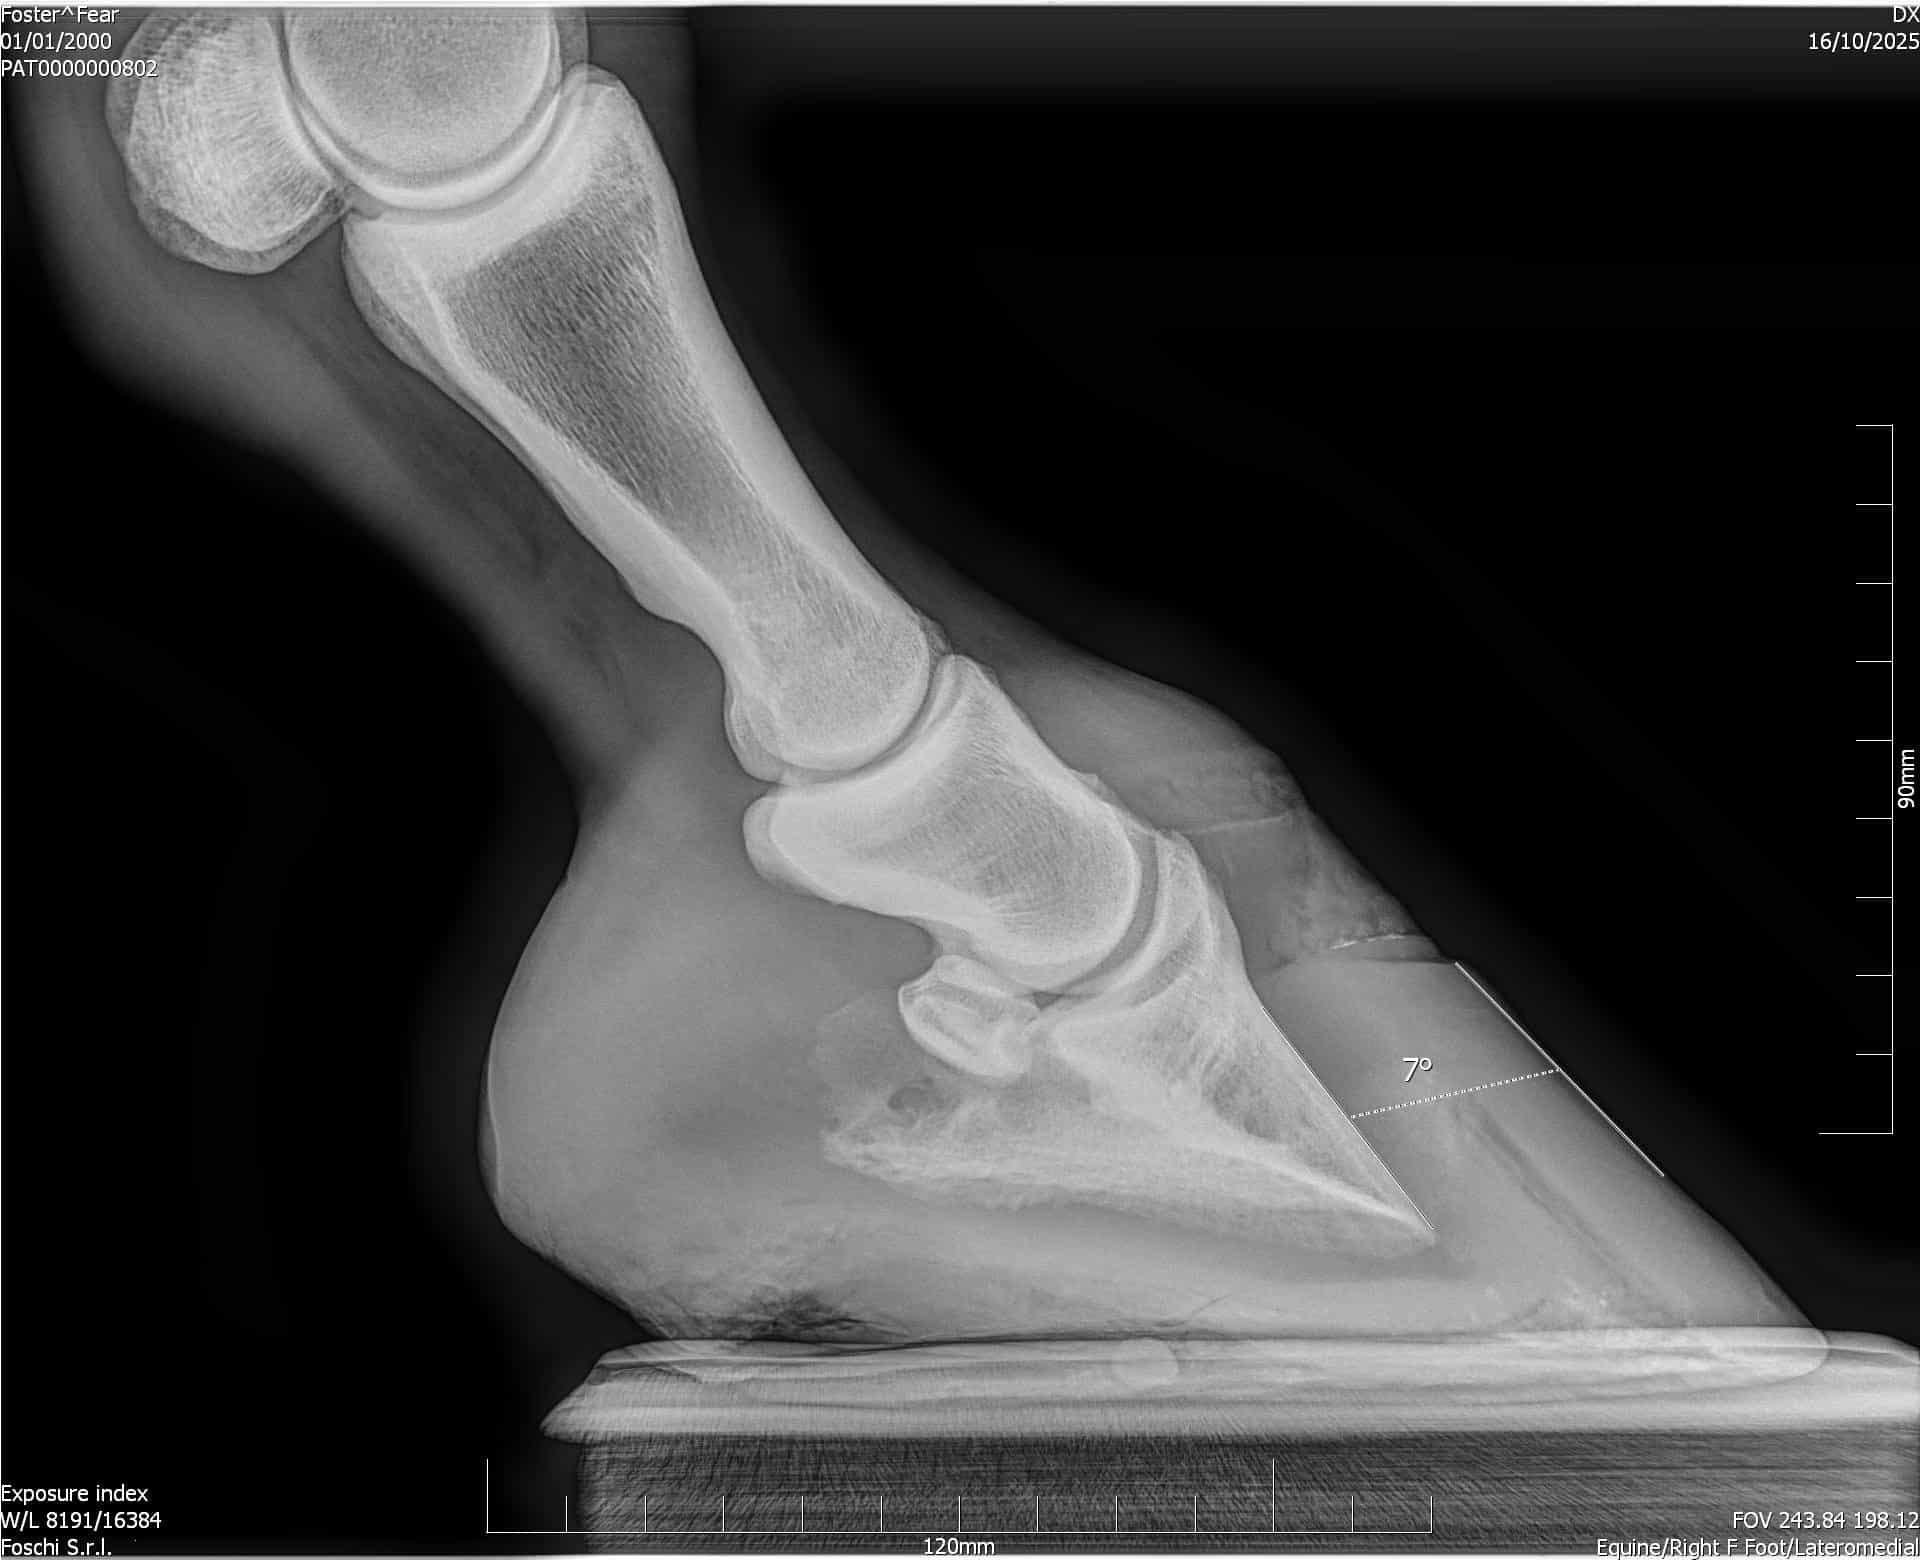

Radiographs and Foot Mapping Keep Your Horse’s Hooves Healthy Introduction Maintaining hoof balance is essential for equine soundness. Even superficial hoof issues can mask deeper imbalances within the hoof capsule. Radiographs—commonly X‑rays—provide a window into the bones and soft tissues beneath...

Biomechanical Rationale for Plantar Heel Extensions in the Management of Chronic Hindlimb Proximal Suspensory Desmopathy Caldwell M and Madden N. Scientific Horseshoeing Limited. 116, Newcastle Road, Talke, Staffordshire. ST71SA. Email info@hoofflix.com Introduction Chronic proximal suspensory ligam...

Chronic Proximal Suspensory Ligament Desmopathy in Horses: Biomechanics, Postural Adaptation, Hoof Capsule Morphology, and Treatment Strategies Caldwell M. N. Scientific Horseshoeing, 116, Newcastle Road, Talke, Staffordshire. ST7 1SA. Email info@hoofflix.com 1. Introduction Chronic desmopathy of th...